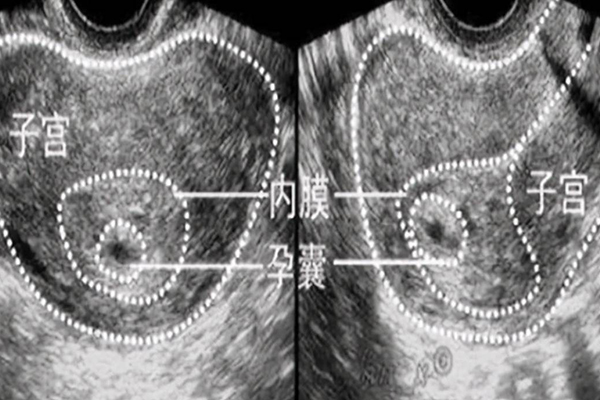

女性同房后,對受精卵著床、生長、發(fā)育的情況非常好奇,聽說受精卵著床期間會有疼痛感,很多女性會有些擔憂,想知道胚胎著床是一直疼還是偶爾疼以及受精卵著床疼痛持續(xù)時間多久等,其實受精卵著床只有少部分女性會有偶爾疼痛感,基本上疼痛都比較輕微都能忍受。少數(shù)還伴隨有出血癥狀,臥床休息后,該情況會自行好轉。

一般來說,受精卵著床期間部分女性可能會出現(xiàn)偶爾疼痛的癥狀,且多為陣發(fā)性,疼痛還很輕微,個別女性還會有小腹部隱隱的疼痛和酸脹的感覺,因為著床以后會引發(fā)子宮局部的痙攣,出現(xiàn)陣發(fā)性的隱痛和酸脹的感覺,這種疼痛輕微,很多人都可以忍受。

通常受精卵著床疼痛時間會持續(xù)3天-5天左右,具體根據(jù)個人的體質(zhì)情況而不同,也沒有確切時間,部分女性著床疼痛持續(xù)的時間較長,通常類似于月經(jīng)來潮前出現(xiàn)的不舒服感覺,一般都在承受的能力范圍內(nèi),有極少女性可能會伴有陰道少量出血,經(jīng)過適當?shù)呐P床休息后,著床疼痛感或陰道少量出血的情況也會自行好轉。